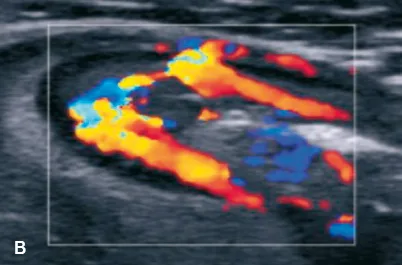

Le Doppler couleur doit être utilisé pour mettre en évidence l’hypervascularisation de la paroi pathologique, traduisant l’inflammation (Fig. 1b) [2].

Figure 1. Patient de 19 ans présentant une poussée aiguë de maladie de Crohn.

B. Échographie Doppler en coupe longitudinale montrant une hypervascularisation de la paroi digestive